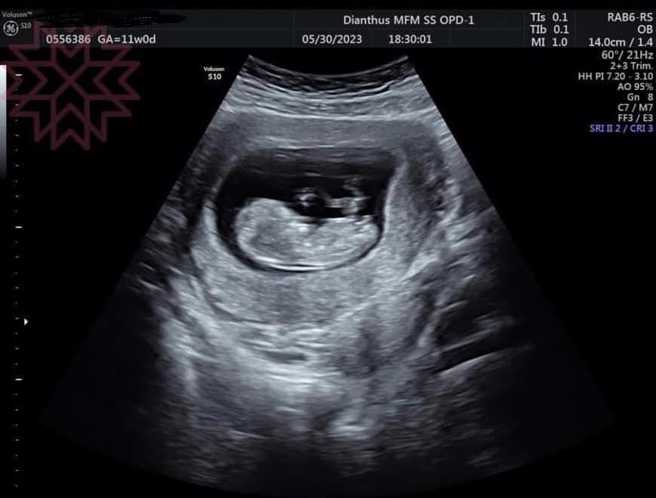

杨绣惠PO超音波照求恭喜。(图/FB@杨绣惠)

眼尖的网友发现,杨绣惠的超音波照的左上角名,是1992年生的柯姓女子,笑说:「左上方有准妈妈的名字」、「老实说:妈妈是谁……」杨绣惠后来把左上角的名字打上马赛克,至今未松口真相。